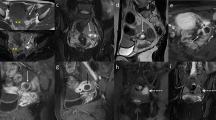

Pyosalpinx in a 47-year-old woman. (a) Sagittal T2-weighted and (b) coronal fat-suppressed T2-weighted images show distended left fallopian tube with low to intermediate signal intensity content (white arrows). (c) Axial DW image (b = 800 s/mm2) and (d) corresponding ADC map show that the lesion’s content demonstrates restricted diffusion with high signal intensity (white arrow) on DWI image and low signal intensity (white arrow) on ADC map, a finding consistent with purulent content. (e) Sagittal and (f) coronal contrast-enhanced fat-suppressed T1-weighted images show the thickened, enhancing wall of the dilated tube (white arrows). (g, h) Histologically, leukocytes, histiocytes, few lymphocytes and plasma cells were evident within the wall (H&E 80X). Tubaric lumen showed fibrin strands, leukocytes, and amorphous material (H&E 300X)

Acute purulent salpingitis in a 62-year-old woman with sigmoid colon diverticulitis. (a, b) Axial T2-weighted images show a distended left fallopian tube with low to intermediate signal intensity content (white arrows); posteriorly the tube is not separable from the sigma, presenting multiple diverticular formations (white arrowhead in a). (c) Axial contrast fat-suppressed T1-weighted image shows marked enhancement of tubaric wall (white arrow) and surrounding fat tissue (white arrowhead). (d) Axial DW image (b = 800 s/mm2) and (e) corresponding ADC map show that the lesion’s content demonstrates restricted diffusion with high signal intensity (white arrow) on DWI image and low signal intensity (black arrow) on ADC map, a finding consistent with a purulent content. (f) Histological sample showed purulent material and many leukocytes in the lumen of the tube and confirmed the presence of mucin-containing regular columnar epithelium lining a mucinous cystadenoma (H&E 300X)